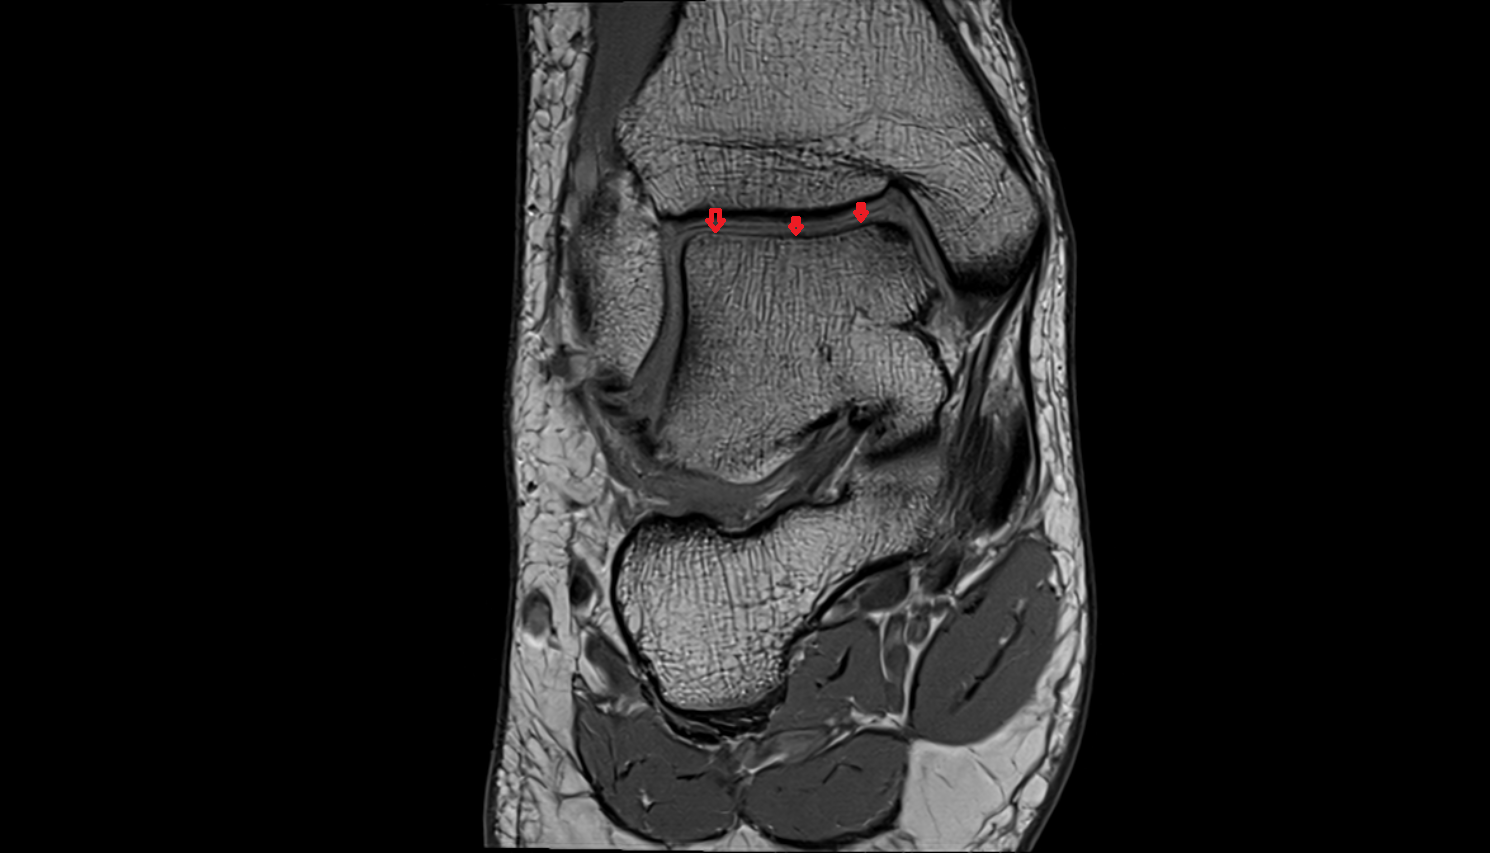

- Temporomandibular joint

- Articular disc of temporomandibular joint

- Articular eminence

- Mandibular condyle

- Mandibular fossa

- Articular surface of mandibular fossa